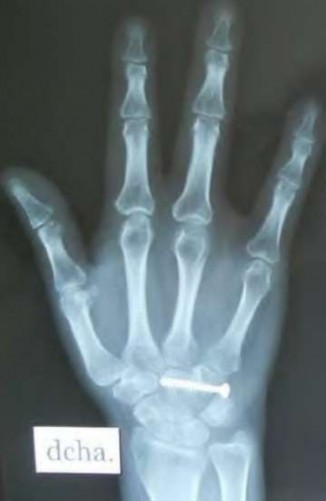

A 35-year-old woman reports wrist pain after a fall onto an outstretched hand. On exam, she has focal tenderness over the wrist snuffbox. A radiograph and CT image are shown in Figures A and B. What is the proper treatment of her injury?